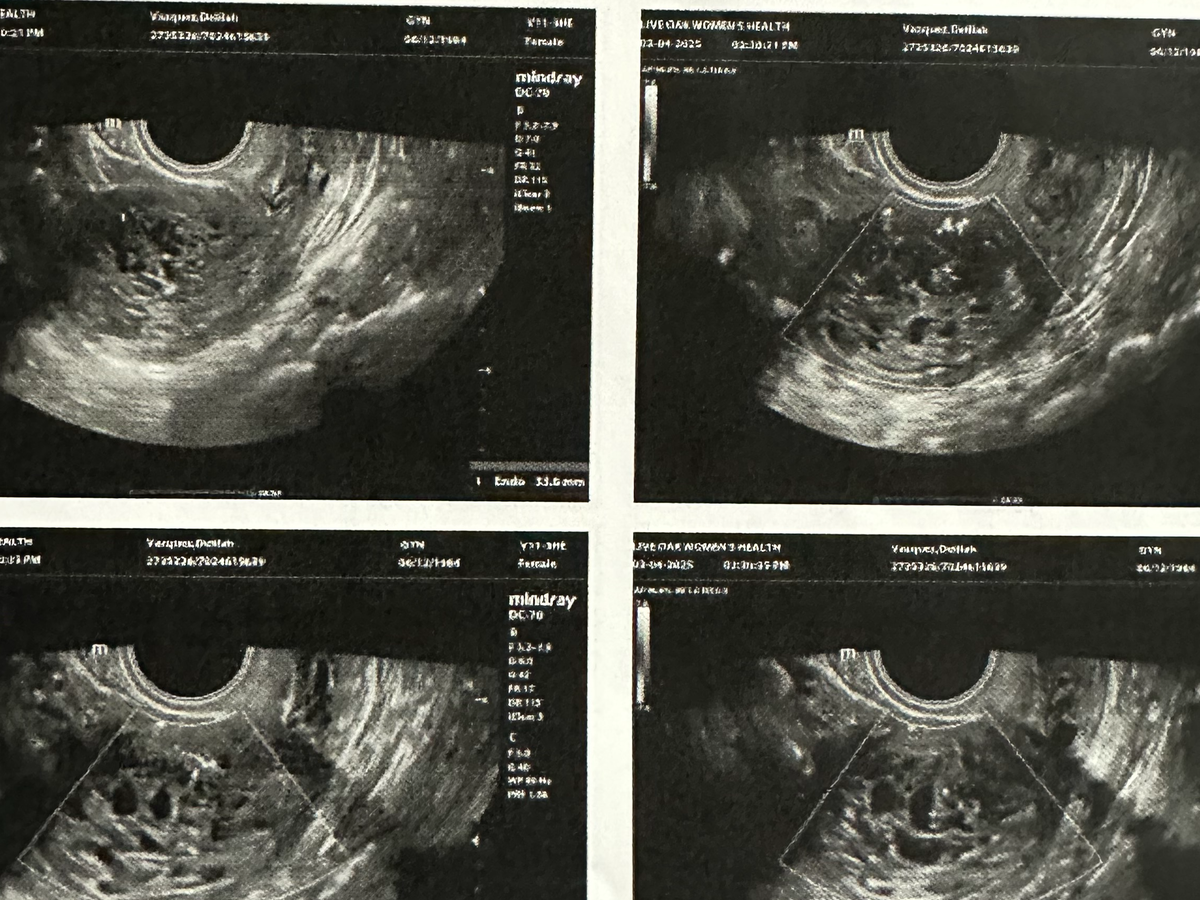

I recently found out that I have a cyst in my ovaries and uterus that require me to have surgery and then they will be biopsied. It’s scary, to say the least. My doctors are still figuring out the best course of action, but there’s a real chance I will need a full hysterectomy. The thought of this surgery (a second surgery)—of what it means for my future—has been overwhelming. Some days, I feel strong. Other days, the fear creeps in.

On April 16th, I underwent surgery where both of my ovaries were removed, along with multiple cysts. As a result, my body has now entered surgical menopause. One of the hardest parts to process is that my dream of becoming a biological mother has been taken from me. That reality has shattered me.